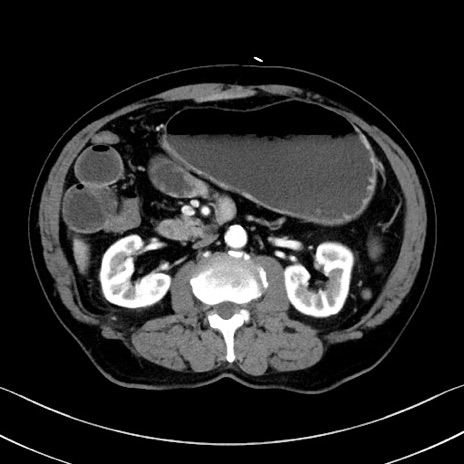

症例35(横断像)

【症例】70歳代 男性

【主訴】腹部膨満、嘔吐

【現病歴】昨日より腹部膨満感出現。本日増悪し、仙痛出現。嘔吐あり、受診。

【既往歴】糖尿病、胆摘後

【身体所見】BP 149/80mmHg、HR 74/min、BT 35.9℃、腹部:膨満、軟、圧痛なし。腸雑音減弱あり。上腹部正中切開瘢痕あり。

【データ】WBC 13500、CRP 1.72